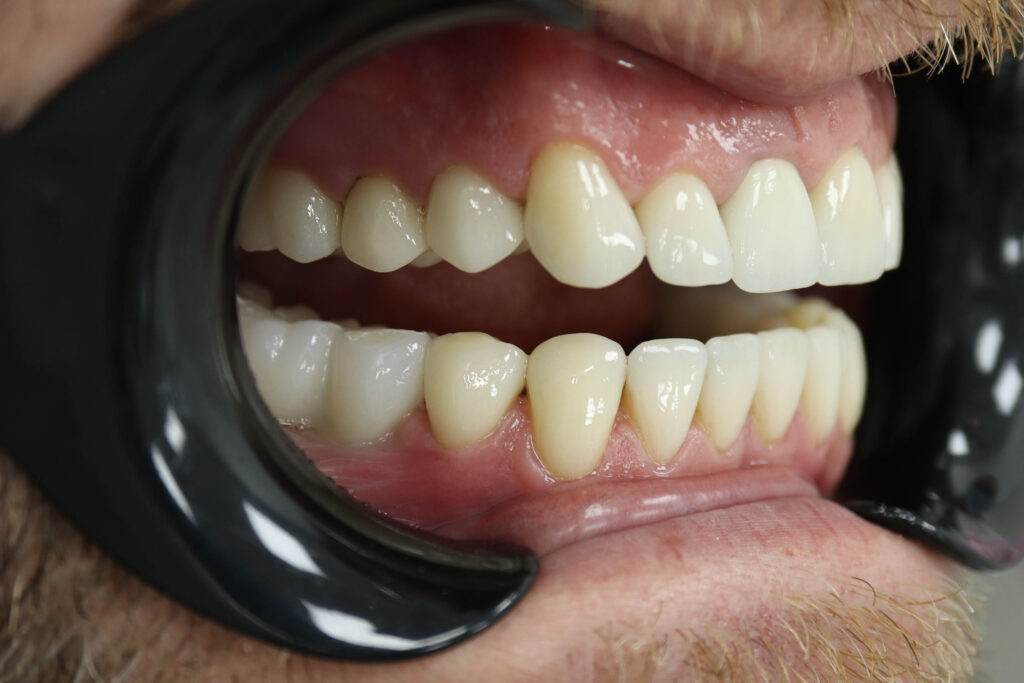

Результаты

Результат протезирования и имплантации